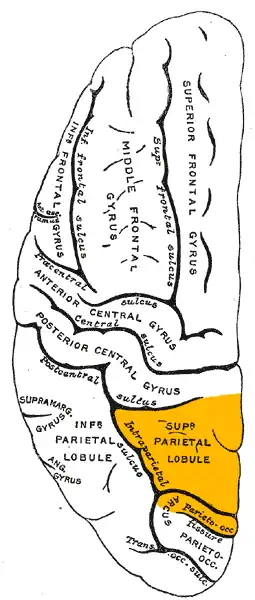

Lateral surface of left cerebral hemisphere, viewed from above. (Superior parietal lobule is shown in orange.) | |